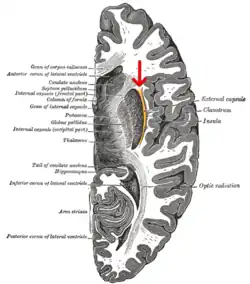

![]() Horizontal section of right cerebral hemisphere. (external capsule shown in orange, indicated by red arrow.) | |

The external capsule is a series of white matter fiber tracts in the brain. These fibers run between the most lateral (toward the side of the head) segment of the lentiform nucleus (more specifically the putamen) and the claustrum.

The white matter of the external capsule contains fibers known as corticocortical association fibers. These fibers are responsible for connecting the cerebral cortex to another cortical area. The capsule itself appears as a thin white sheet of white matter.[1]

The putamen separates the external capsule from the internal capsule medially and the claustrum separates it from the extreme capsule laterally. But the external capsule eventually joins the internal capsule around the lentiform nucleus.